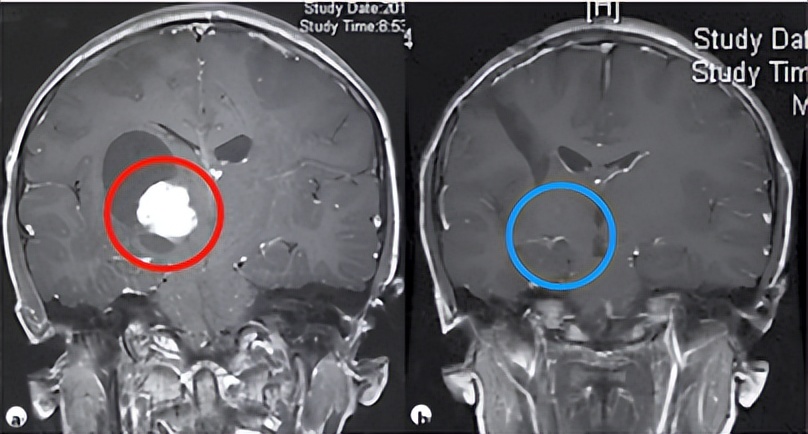

有些良性脑肿瘤因为位置复杂,手术切除困难,且面临瘫痪、部分神经功能丧失等风险时,如能找到世界范围内能胜任这一手术达到安全全切的神经外科专家主刀手术,孩子也将有极大的治愈希望。以以下一则来自加拿大多伦多大学儿童医院SickKids脑瘤研究中心主席James T. Rutka教授的一个9岁右丘脑胶质瘤患儿为例,他幸运地获得了全切,最终的组织病理学诊断是毛细胞星形细胞瘤,有多个医学论文证明这种低级别胶质瘤中位生存期可达50年。如今,小朋友早已恢复了正常的学习生活,他经常忘了自己曾是个脑瘤患者。

术前(a)和术后(b)的脑MR图像,来自Rutka教授公开发布的手术案例